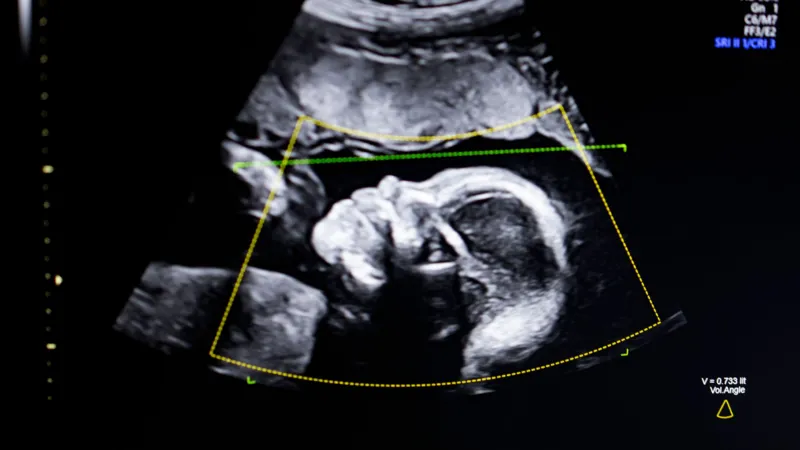

Getty ImagesThe SoR is now calling for sonographer to become a protected job title in the UK in the same way as dietician, podiatrist, art therapist or radiographer.

That would mean only those who are properly qualified and registered with a regulatory body would be allowed to use that job description.